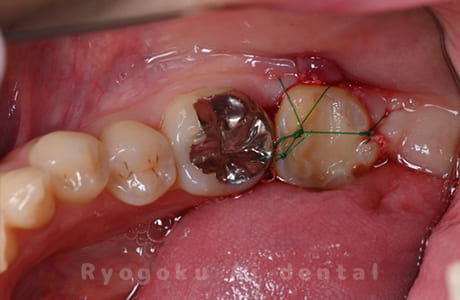

Case08

-

- 原因

- 歯根嚢胞、重度カリエス

- 治療内容

- 再植手術、クラウンレングスニング

- 治療費用

- ¥99,000

他院で根管治療を行ったが、なかなか治らず、抜歯を宣告されたとのことでご来院された患者様です。歯がかなり削られており、また、歯根の根尖部の病変が大きく、嚢胞化しているため、クラウンレングスニングと再植歯根端手術を同時に行いました。違和感もなくなり、大変満足されています。

<リスク・副作用>

外科手術のため、術後に出血、痛みや腫れ、違和感を伴います。口腔内の状態によっては適応できないことがあります。歯根端切除で治らなければ抜歯を検討しなくていけない場合もあります。